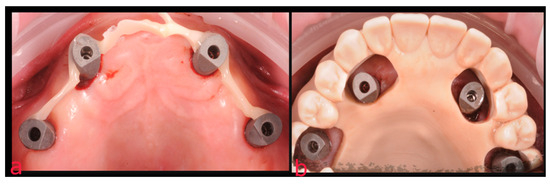

2.1. First Step: Complete Fixed Rehabilitation

2.2. Second Step: From FDP to Implant-Supported Overdenture